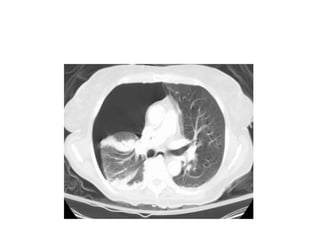

Figure 28a. Xảo ảnh thể tích từng phần ở bn nữ 52 tuổi. Lâm sàng có khó

thở.

(a) Lát cắt có độ dày 3.75 mm, giá trị trung bình thể tích của mạch máu và

phổi tạo nên xảo ảnh giống như PE ở đm phân thùy trước của thùy trên

phổi trái. (mũi tên). Nhưng hình ảnh này có giới hạn không rõ.

3

7